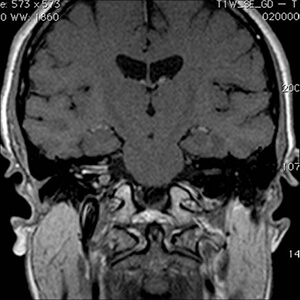

Προεγχειρητικές εικόνες μαγνητικής τομογραφίας ασθενούς 42 ετών με ακουστικό νευρίνωμα δεξιά με πίεση επί του στελέχους